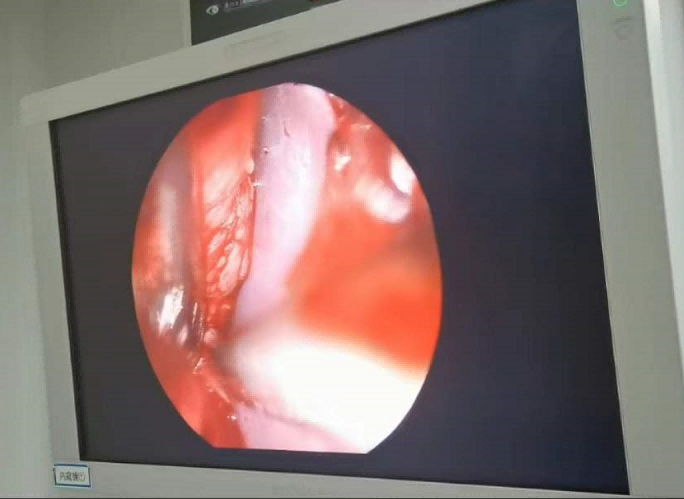

送到廈門(mén)眼科中心的時(shí)候,林老師受傷的左眼還在流血。眼整形科的鄧?yán)っ鞲敝魅吾t(yī)師緊急為他安排了“內(nèi)鏡下眶骨折修補(bǔ)+鈦網(wǎng)鈦釘植入術(shù)”。

圖為:內(nèi)鏡下眼眶骨折修補(bǔ)術(shù)

手術(shù)過(guò)程中林老師還出現(xiàn)了驚險(xiǎn)的眼球后大出血,還好鄧?yán)っ饔诰o急之中穩(wěn)住了病情,并順利完成了手術(shù)。術(shù)后第二天,林老師的術(shù)后反應(yīng)就很輕,恢復(fù)良好,他一邊感謝著鄧?yán)っ鞯?ldquo;救命之恩”,一邊自嘲著自己示范了個(gè)“反面教材”。